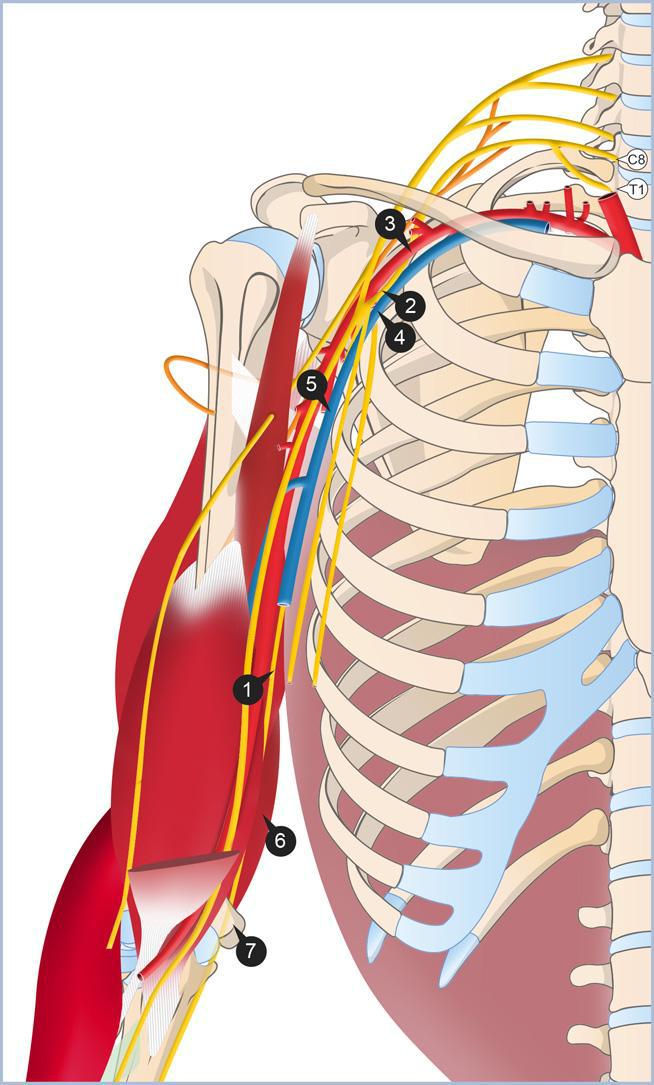

LES RAPPORTS VASCULAIRES

- l’artère brachial est accompagnée sur toute sa longueur par les deux veines brachiales

- Par les branches terminales du plexus brachial

- Par les groupes ganglionnaires lymphatiques de la région brachial

LES RAPPORTS NERVEUX

- Les branches terminales du plexus brachial sont placées en avant et latéralement

- le nerf médian en avant de l’artère

- Le nerf musculo-cutané situé en dehors de l’artère ,puis perfore le muscle coracobrachial

- Le nerf ulnaire médialement puis quitte le canal brachial

- Le nerf cutané médial du bras dans le tiers supérieur du canal brachial

- Le nerf médial cutané de l’avant bras qui quitte le canal brachial dans sa portion distale

RAPPORT AVEC LES BRANCHES TERMINALES DU PLEXUS BRACHIAL